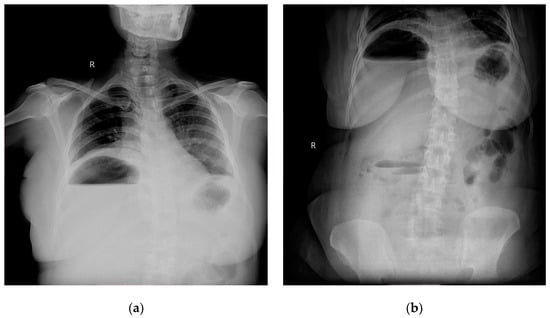

Figure 1. (a) Chest roentogram showing air fluid level in the right upper abdomen; (b) abdominal radiogram showing air fluid level in right upper with some fluid levels in central abdomen as well.

Radiographic investigations revealed large air fluid level under the right diaphragm with multiple air fluid levels in the right upper part of the abdomen (Figure 1a,b).

Abdominal ultrasound, simple abdominal radiography, and other imaging techniques are useful for diagnosis, but CT is the best method for sensitive detection of gas within abscesses. In the present case X-ray showed air under right dome of Diaphragm and as patient was clinically stable, CECT was done which confirmed the diagnosis.